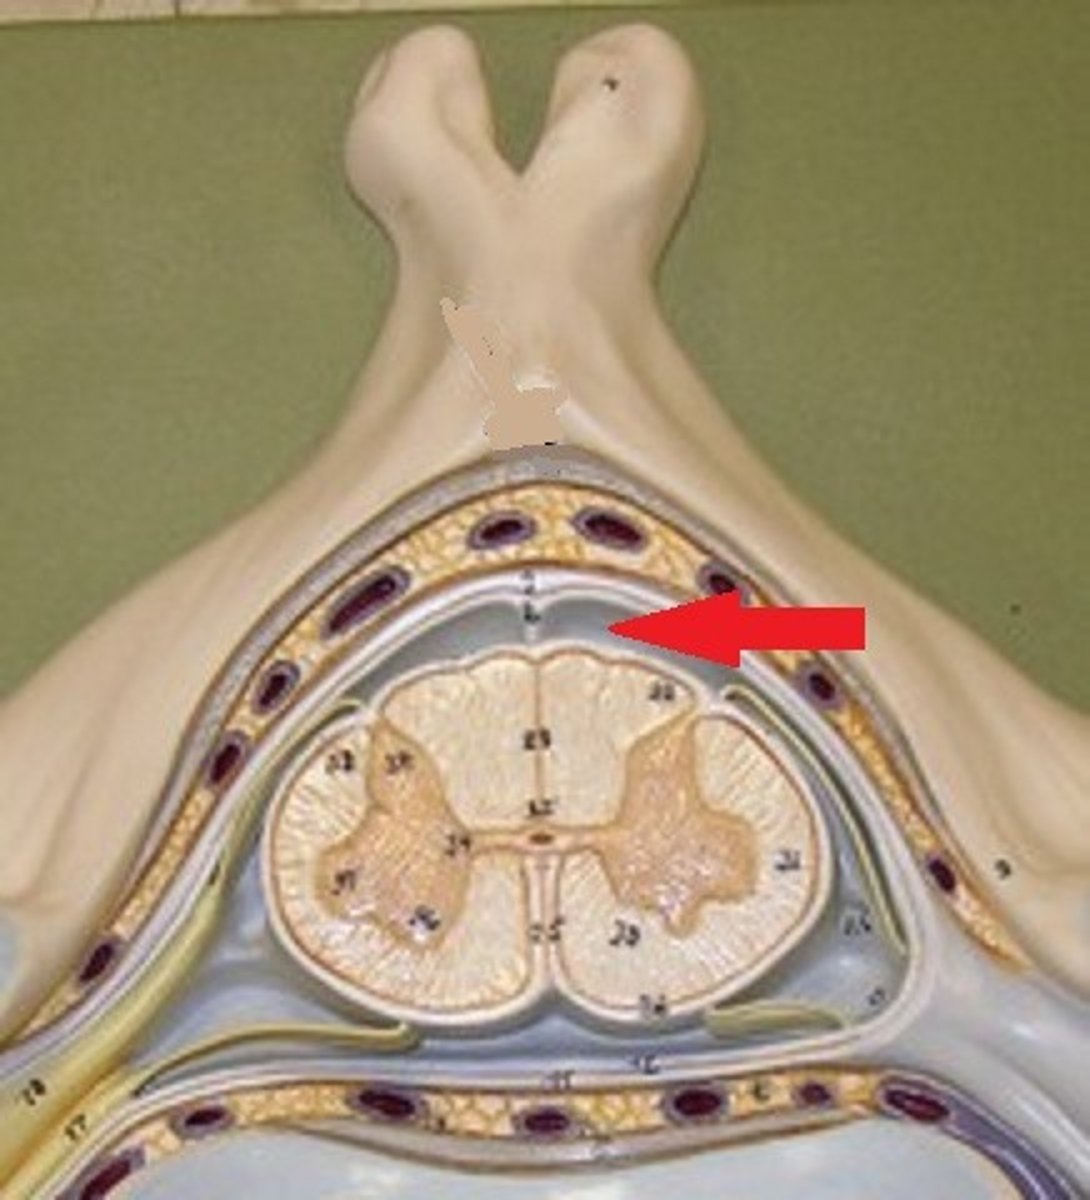

subaracnoid space (part of meningies)

subarachnoid space anatomy

subachnoid space

where does the spinal fluid flow

subarchnoid space

covers that cover spinal cord and brain

what are the menengies

dura mater, archnoid mater, pia mater

what are the layers of the menengies from outer to inner

between the archnoid mater (under it) and the pia mater

where is the subarchnoid space in the menengies

gray mater spinal